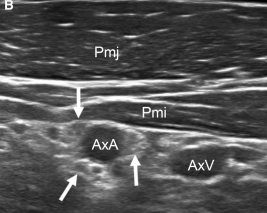

초음파를 이용해

아프지 않은 정상적인 쪽을 먼저 보고

그 다음에 아픈 쪽을 비교했습니다.

신경이 얼마나 부어있는지,

주변 조직과 유착되어 눌려있는지를 분석한 결과,

MRI와 비슷한 수준으로

상완신경총의 문제를 찾아낼 수 있었습니다.